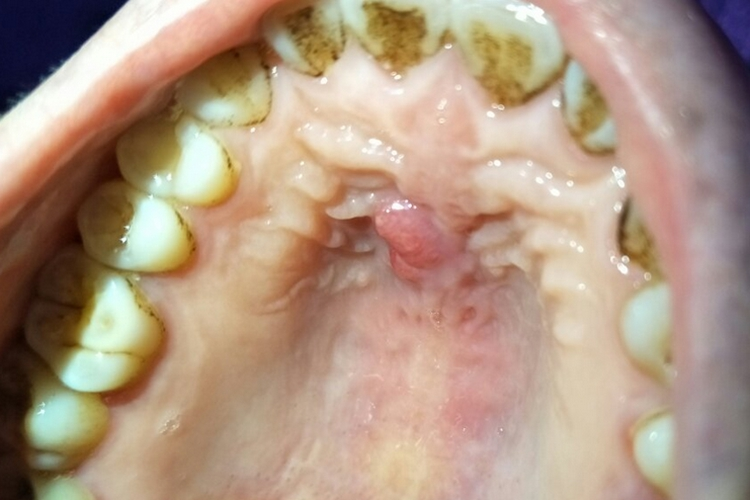

左侧上颌窦粘膜下囊肿是发生在左侧上颌窦内的一种常见良性病变具体如下定义与发病机制上颌窦属于鼻窦的一部分,为鼻腔周围含气的骨质空腔粘膜下囊肿通常因窦粘膜的粘液腺或浆液腺导管阻塞,导致粘液潴留形成囊性肿物,一般呈半球形,内含粘液样或浆液样物质其发病机制可能与鼻窦慢性炎症变态反应。